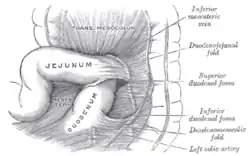

Superior and inferior duodenal fossæ. | |

Duodenojejunal fossa.

Duodenojejunal fossa.